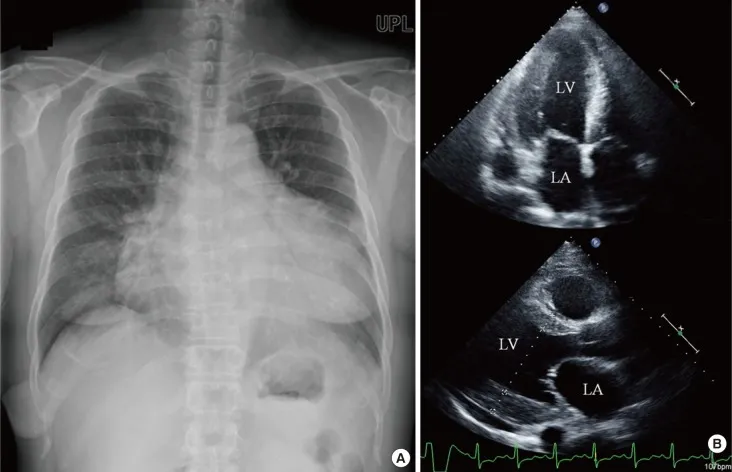

- Echo: ↑ ventricular wall thickness, "sparkling" or speckled myocardium.

⭐ Classic board question: Suspect cardiac amyloidosis with the triad of heart failure, low-voltage ECG, and increased ventricular wall thickness on echocardiogram.

- Amyloidosis: Causes restrictive cardiomyopathy with a classic low-voltage ECG despite ventricular hypertrophy.